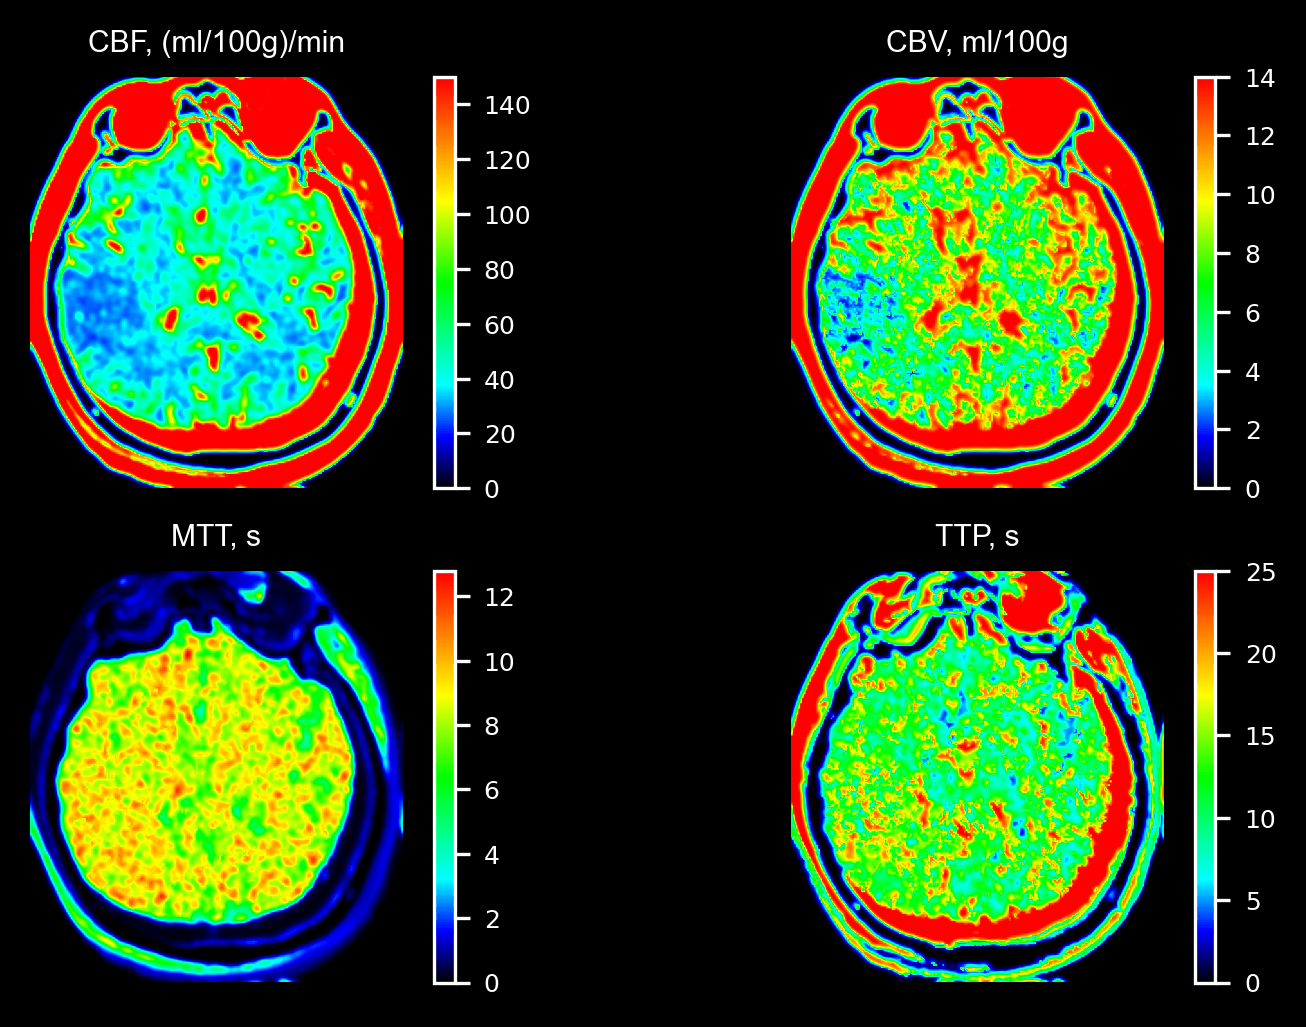

Модуль расчета параметров кровотока по данным КТ для клиент-серверного медицинского ПО

Разработка модуля расчета параметров кровотока головного мозга по данным КТ для большого клиент-серверного медицинского ПО. В наши обязанности входили:

1. НИР по мед. физике

2. Разработка модуля

3. Тестирование на DICOM-данных

4. Дополнительный модуль для зеркального сравнения параметров левого и правого полушарий мозга

Модуль использован в ПО, которое внедряется в лечебных учреждениях РФ.